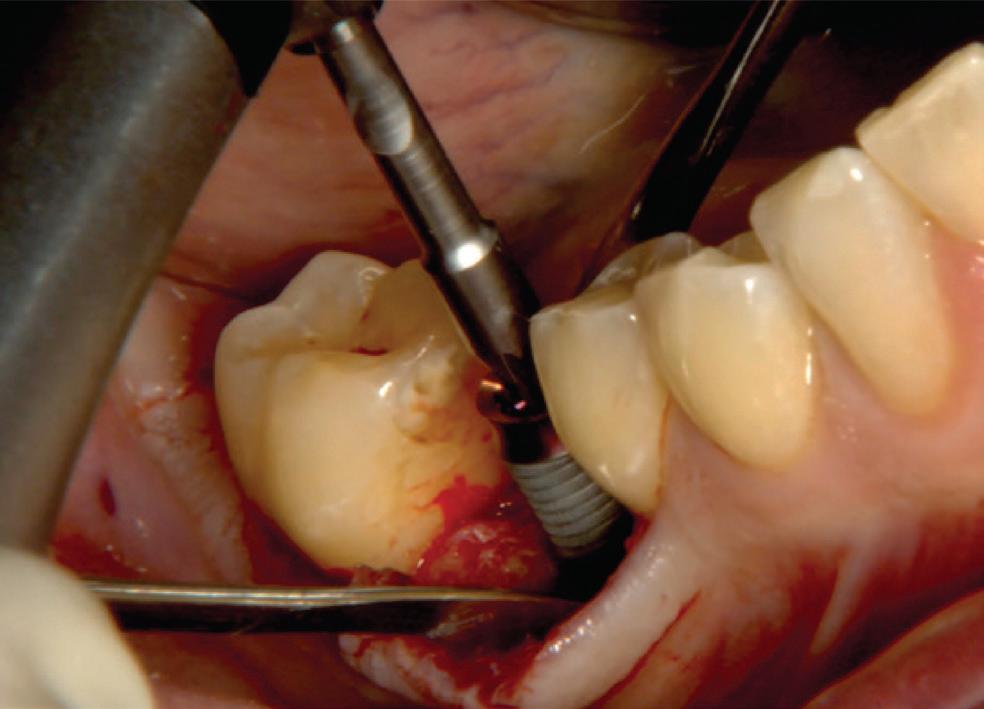

In 1975, one of my patients who was 18 years old became involved in a car accident; he hit the steering wheel with his chin and sustained 2 horizontal fractures in his 31, both quite a way subgingivally. The 41 and 32 were intact. The normal treatment at that time would have required extraction of the 31 and the placement of a partial denture or a bridge to replace the missing tooth.

Knowing that he had nothing to lose, he agreed to let me experiment on him. I extirpated the 31, drilled 10mm past the apex using a sterile Kurer Post spiral drill that matched the diameter of my titanium wire. I sterilised the Titanium using a

Yes, I did stick my neck out, but the result ended being a lot better for the patient than if we had opted for a bridge or a partial denture. The biological cost was negligible and we bought him 30 years of function until a better and more modern treatment became available.

In the current regulatory environment, treatment such as I described is not only illegal and would result in crippling fines being imposed by the TGA, but possibly result in losing one’s right to practice. If I had made a conventional bridge, the teeth either side would have been compromised and possibly lost by now, a partial denture would have caused periodontal problems.